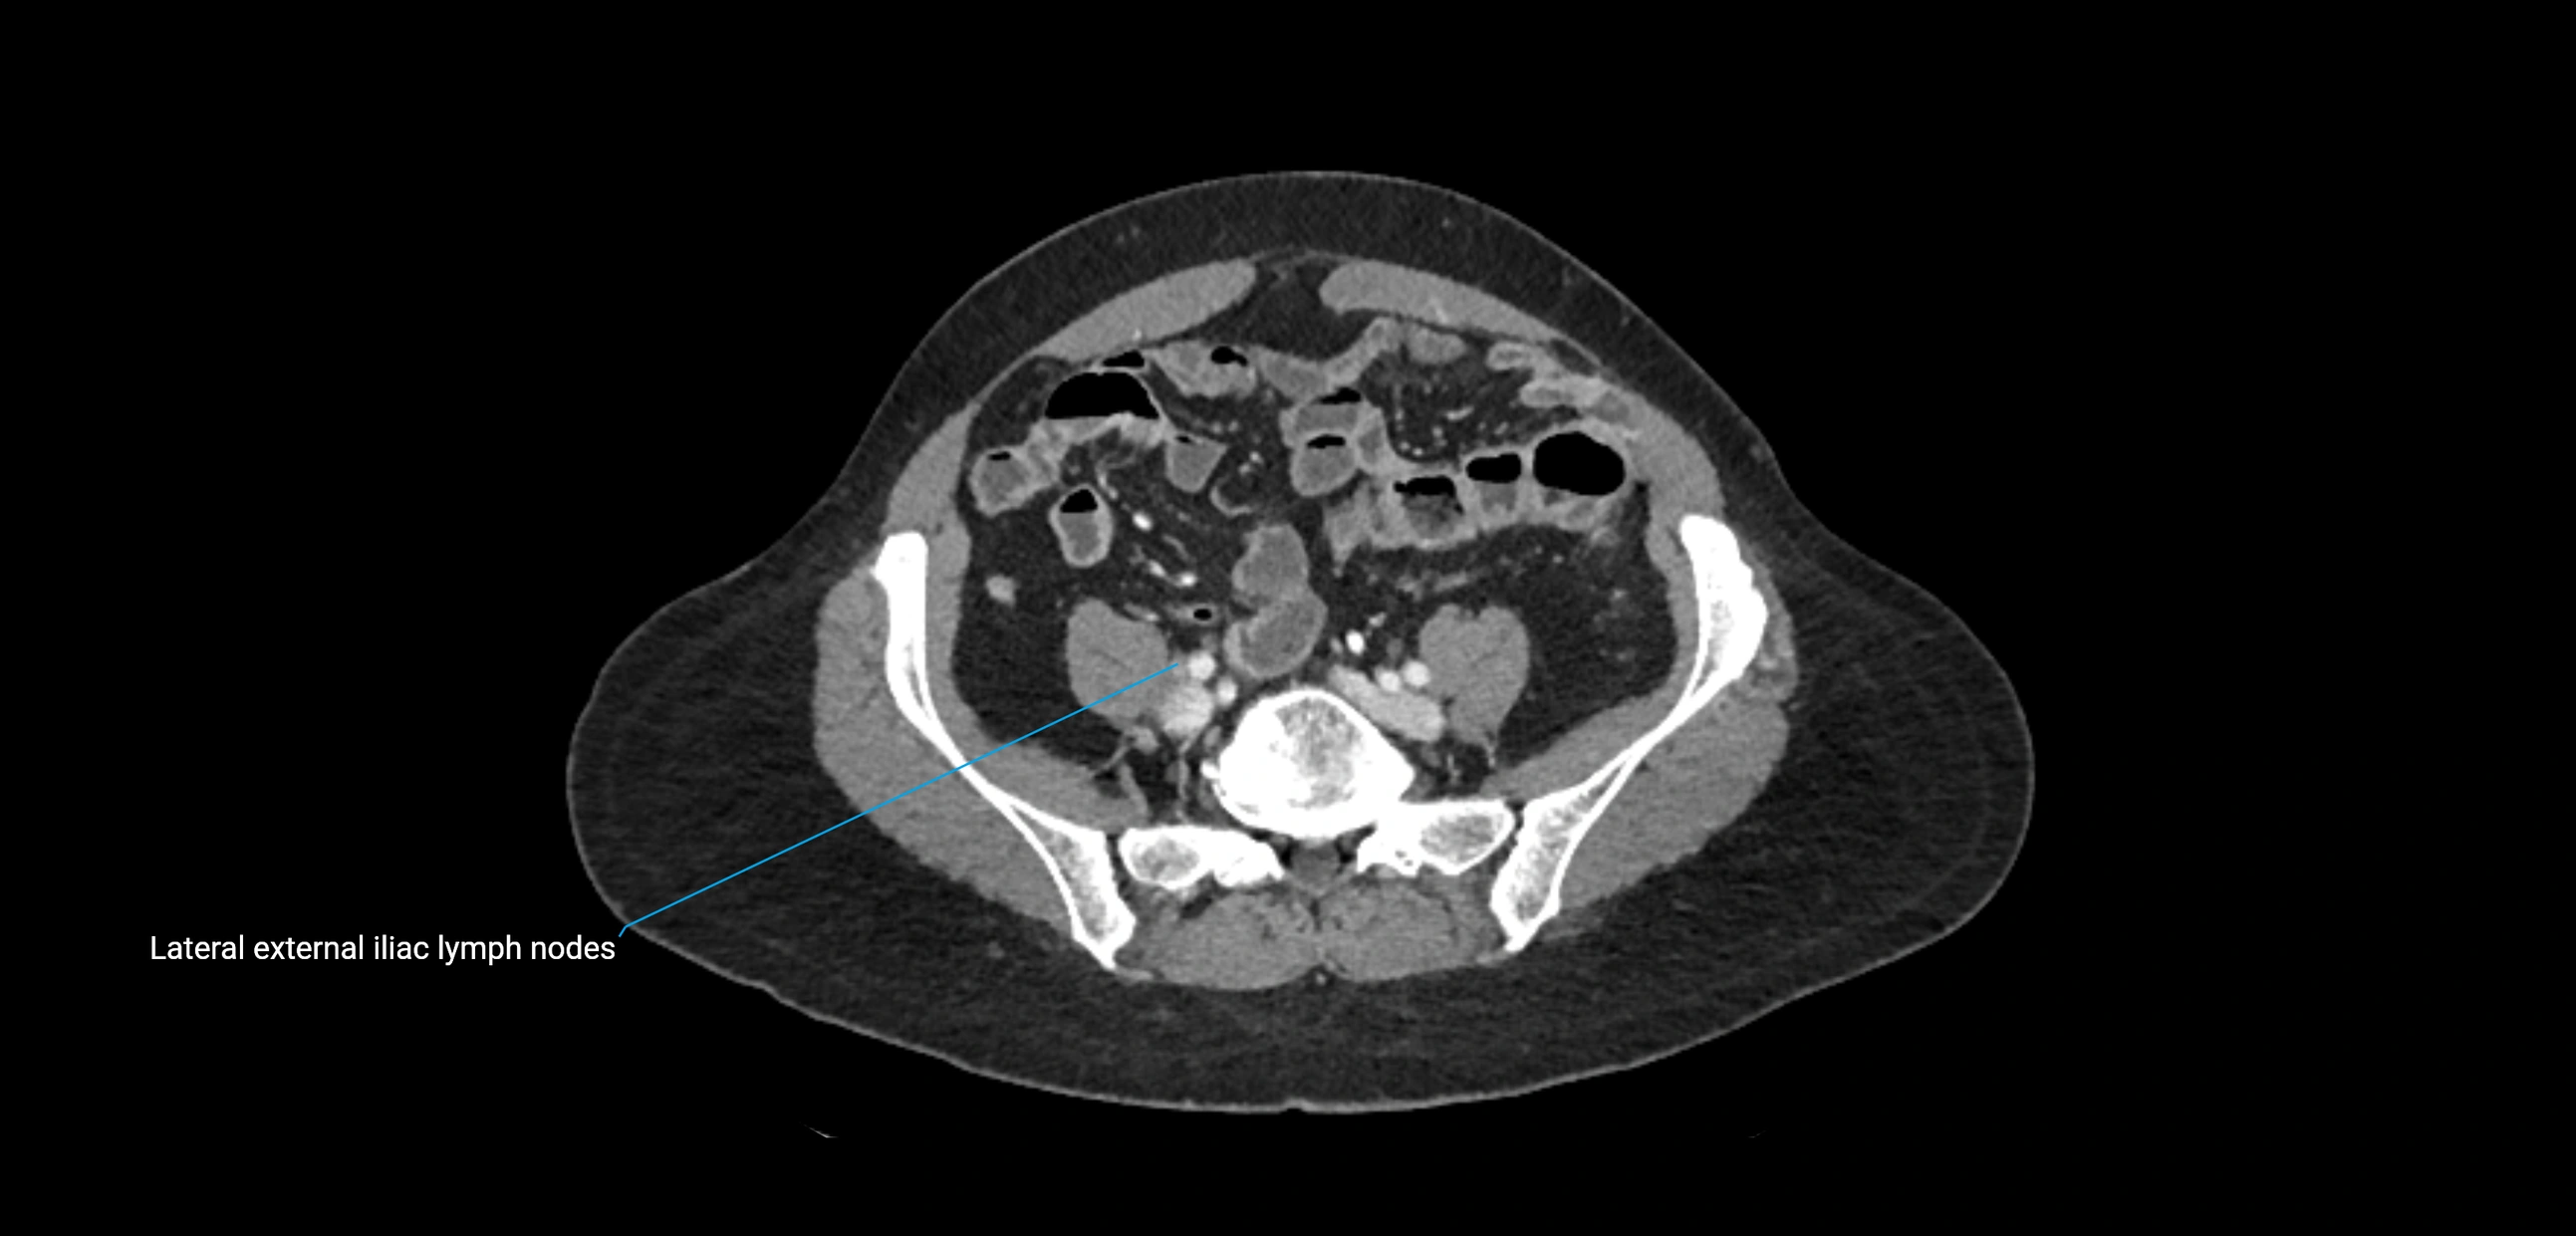

CT Appearance

CT Pre-Contrast:

• Nodes appear as soft-tissue density nodules adjacent to the aorta and IVC

• Calcification may be seen in chronic infections (e.g., tuberculosis)

CT Post-Contrast:

• Normal nodes enhance homogeneously

• Malignant nodes may show heterogeneous enhancement, central necrosis, or conglomerate formation

• Size >1 cm short axis is suspicious, though morphology and distribution are equally important

CT Venography (CTV):

• Demonstrates nodal encasement or compression of adjacent vessels (aorta, IVC, renal veins)

• Useful in staging testicular and ovarian malignancies

• Provides 3D reconstructions for retroperitoneal lymph node dissection planning